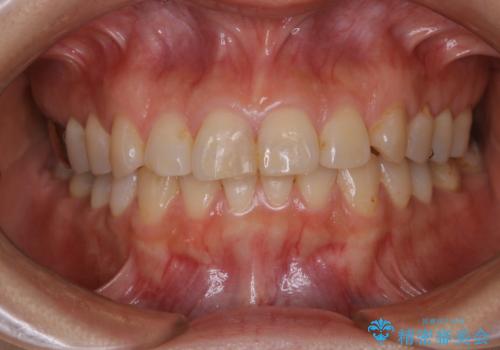

何度も欠けてしまう前歯を被せ物で治療

- プラスチックで治療している前歯が何度も欠けてしまうとお悩みで来院された方です。

歯全体を覆うクラウンにて治療を行いました。

前歯1本のみの被せ物治療を行う場合、他の歯を参考に歯の色や形を忠実に再現することが重要です。オールセラミッククラウン(スペシャル・エクセレント)は、事前に歯科技工士との打ち合わせを行うことで、歯の色や形、さらには患者様のご希望も聴取したうえでクラウンを作製することが可能です。